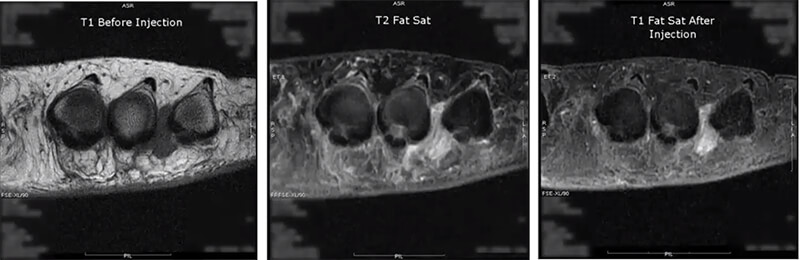

On the fourth image, we are evaluating Morton’s neuroma in T1 and we see that darkened area between two of the toes. Next, we run a T2 fat sat, which suppresses the fat and allows us to see true pathology. Then we run the post-contrast as a T1 injected fat sat. Again suppressing the fat, but notice the contrast enhancement of the lesion now compared to the first T1.